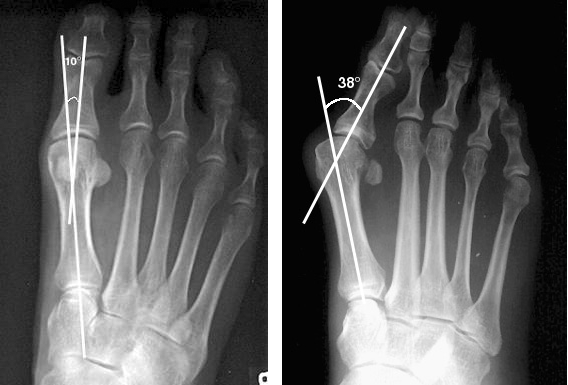

L’objectif n’est pas seulement de « raboter la bosse », mais de réaxer le métatarse.

• L’Ostéotomie : Le chirurgien réalise des coupes osseuses (ostéotomies) pour redresser le métatarse et la phalange. Ces corrections sont fixées par des petites vis qui restent généralement à vie.